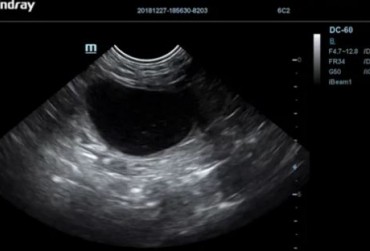

Ciało obce w pęcherzu moczowym jako jądro krystalizacji dla kamienia moczowego – opis przypadku

Zapalenie pęcherza moczowego jest częstą dolegliwością spotykaną w gabinecie lekarza weterynarii. Brak lub nieodpowiednia diagnostyka i leczenie chorób dróg moczowych u psów oraz kotów może prowadzić do groźnych powikłań oraz niepotrzebnie narażać zwierzę na cierpienie. W artykule opisano przypadek kota rasy europejskiej, który został postrzelony ok. 4 lata temu z broni pneumatycznej. Pocisk ze śrutu utkwił w pęcherzu moczowym zwierzęcia oraz stał się jądrem krystalizacji dla kamienia moczowego. W tekście zostały opisane teorie dotyczące tworzenia się kamieni moczowych, metody diagnostyki oraz leczenia kamicy pęcherza moczowego i krystalurii.